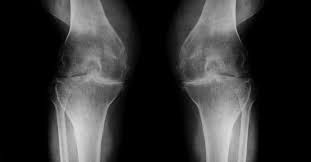

Arthritis is managed best initially by a physical medicine and rehabilitation (PM&R) physician who is highly trained in the conservative treatment of joint and muscle problems. Treatment methods used include weight loss, acetaminophen, NSAIDs, corticosteroid injections, viscosupplementation and rehabilitation. Viscosupplementation has recently become more common as it helps to alleviate arthritis pain through injection of a gel-like substance that mimics the natural lubricant created in the joint to allow more “cushion” within the joint. If pain is still persistent regardless of conservative management, a referral from a PM&R physician to an orthopedic surgeon may be necessary to consider total joint arthroplasty.